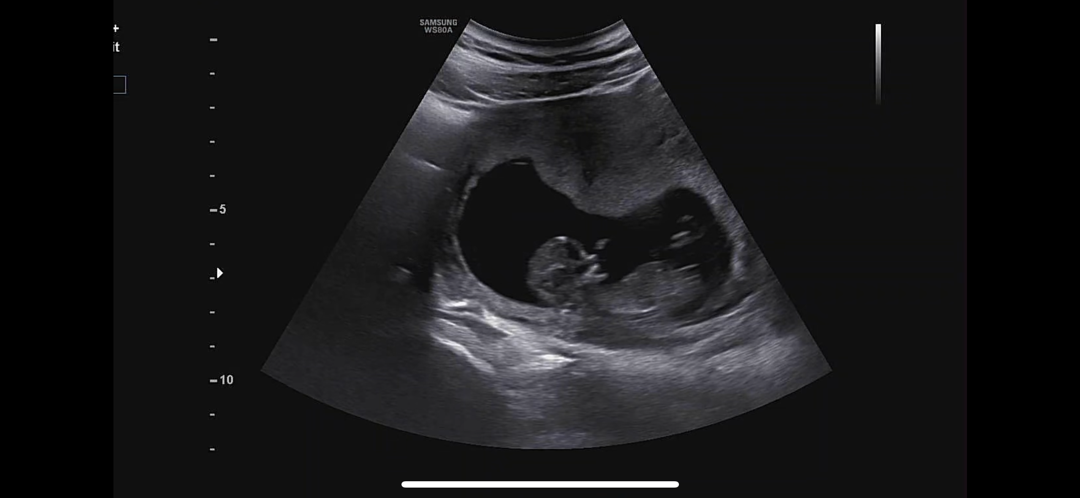

각도법 성별 확인점 부탁드리겠습니다

투표부탁드리겠습니다-!